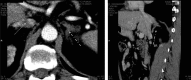

Figure 2. Abdominal computed tomography scan showing bilateral adrenal hyperplasia in a patient with primary hyperaldosteronism.

Patient E.A, male; basal aldosterone level was 209.2 pg/mL, direct renin concentration was 1.9 pg/mL, with aldosterone (ng/dL)/renin (ng/L) ratio of 11. Following 50 mg captopril challenge test, aldosterone failed to suppress more than 30% (175.75 pg/mL).